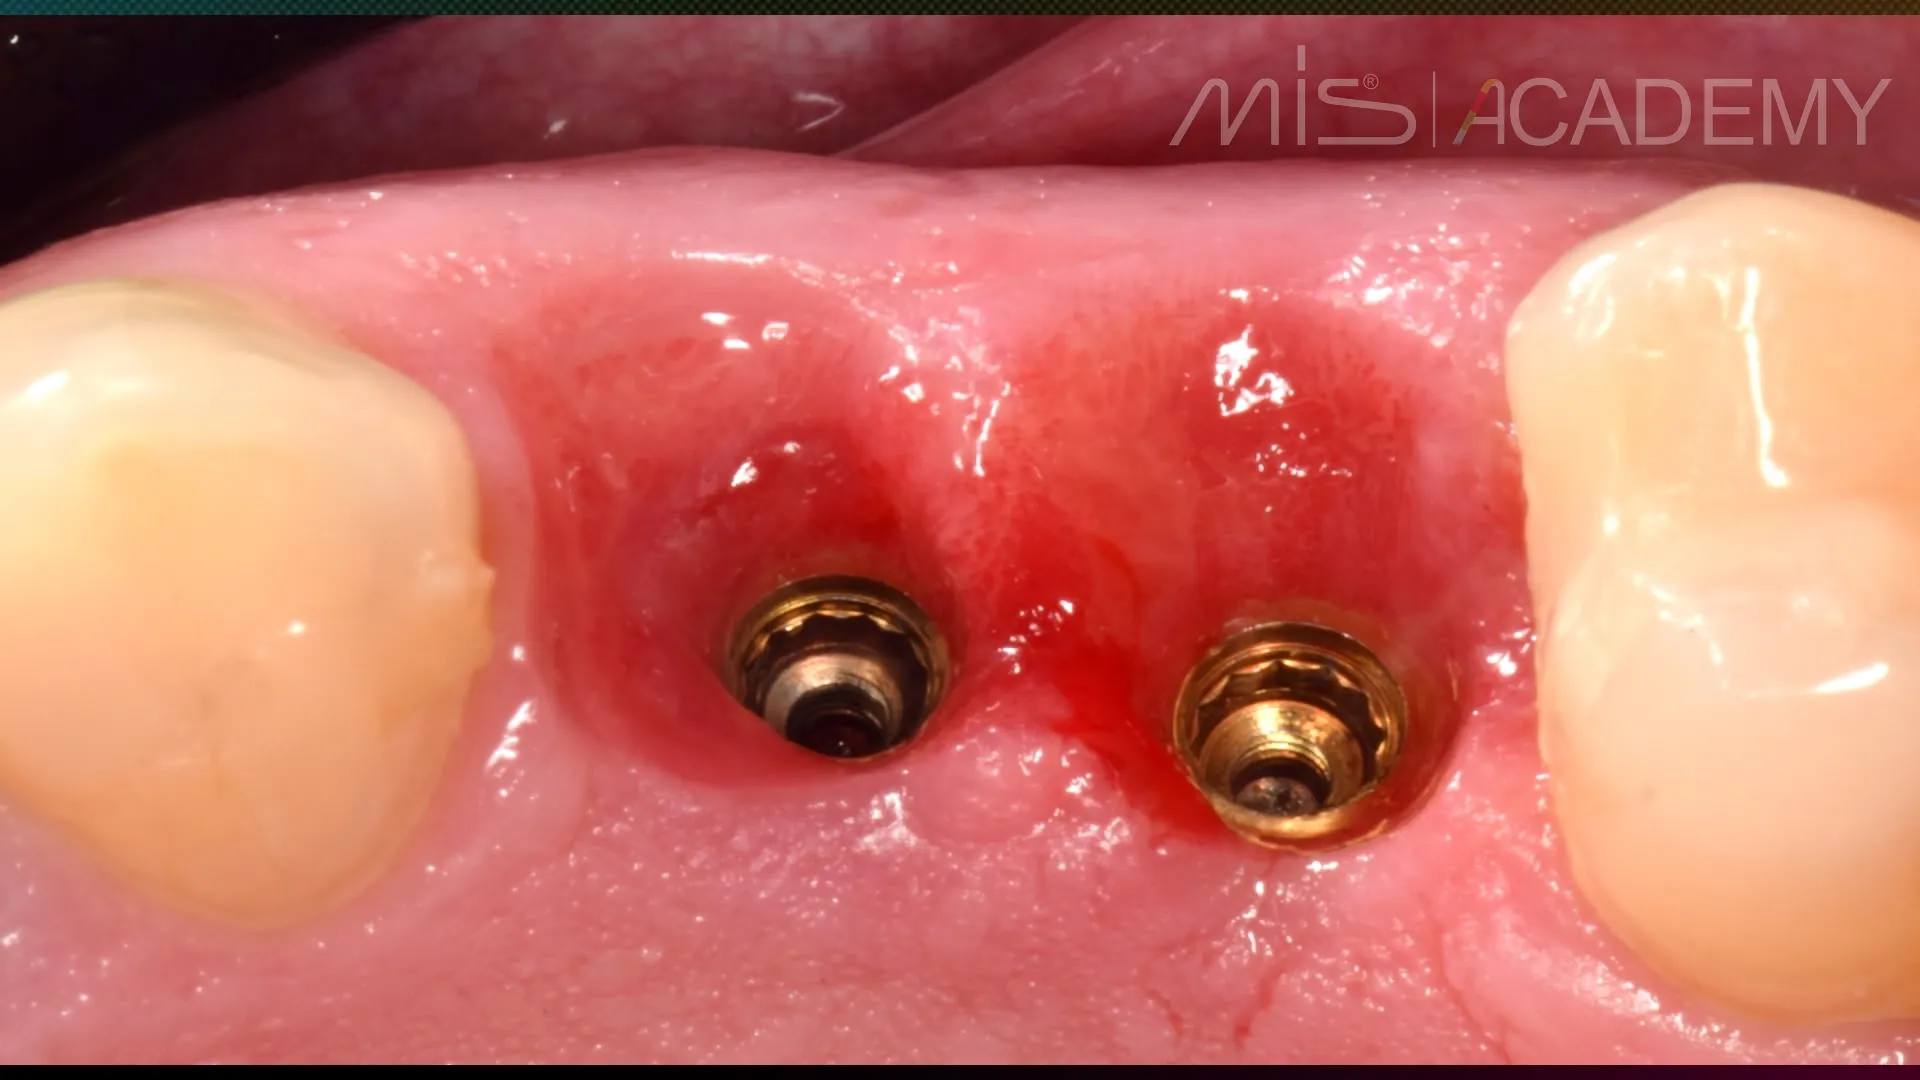

— Временные коронки через 6 месяцев.

— Результат формирования контура прорезывания на временных коронках спустя 1 месяц после их установки.